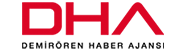

Plastik Rekonstrüktif ve Estetik Cerrahi bölümünden Dr. Burçin Acuner ile birlikte cerrahi işlem planlandı. Yapılan ameliyatta çenenin tümörlü parçası kesilerek temizlendi. Çenesinin yaklaşık 6 santimi dişleriyle birlikte alınan Çakmaklı’nın sol kaval kemiğinden bir parça kesilerek yeni çene yapımında kullanıldı. Çakmaklı’nın hastanedeki tedavisi sürüyor.

Doç. Dr. Deniz Baklacı, “Hasta bize ağızda geçmeyen yara şikayetiyle başvurdu. Yara bölgesinden alınan biyopsi sonucu malign karakterde (kötü huylu tümör) gelmesi sonucu tedavi planlaması yaptık.

Hastalığın kemik komşuluğu olması nedeniyle buradan çıkarılacak parçanın yerine fonksiyonel olan bir organ olması açısından rekonstrüksiyonun yapılması gerekiyordu. Bizim dahil olduğumuz kısım tümörün çıkarılması ve boyunun temizlenmesi, ancak geride kalan boşluk ve çenenin yeniden onarımında biz işi plastik ve rekonstrüktif cerrahi bölümüne devrediyoruz” dedi.